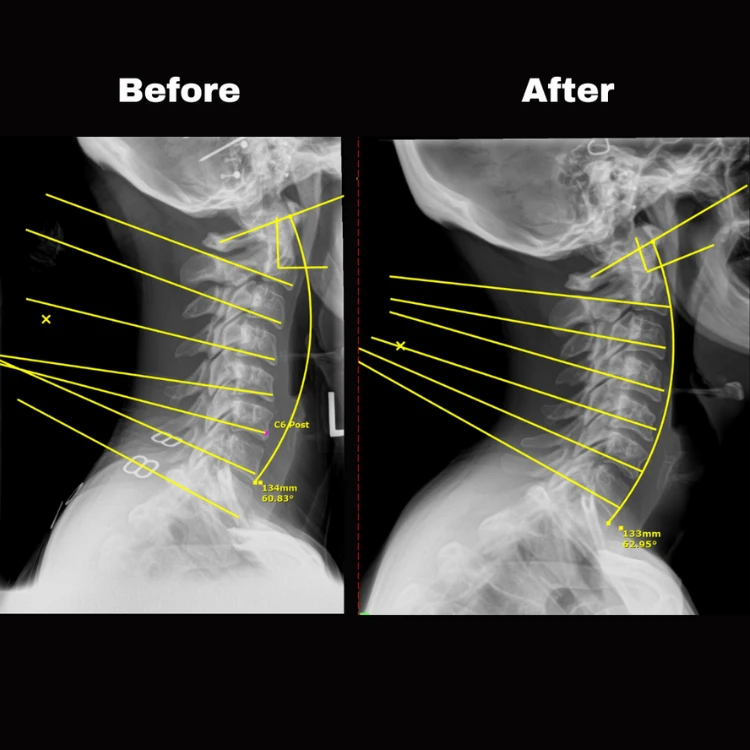

Following your first appointment, Your Doctor will present more information about health, healing and chiropractic care, and answer any other questions you may have. It is vital that you bring your loved ones with you as we will review our findings, including your chiropractic postural X-Rays, our recommendations and however we can make care affordable for you and your entire family.

You will receive your first specific Gonstead adjustment from Your Doctor following the Doctor’s Report. In order to achieve your results as quickly as possible and reach your health goals, it’s vital to be consistent in keeping your appointments and stick to the recommendations given by the doctor.